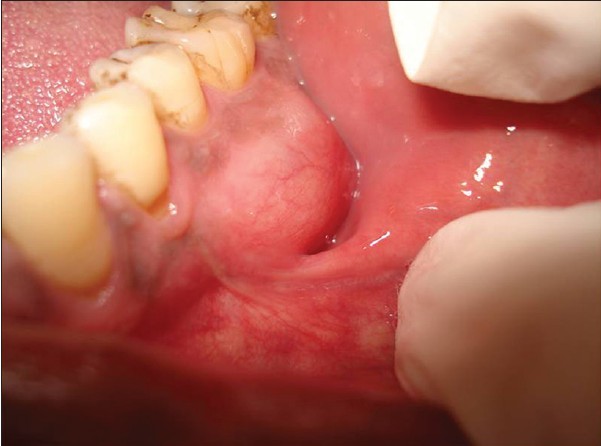

Parotid tumors are abnormal growths of cells (tumors) that form in the parotid glands. The parotid glands are two salivary glands that sit just in front of the ears on each side of the face. Salivary glands produce saliva to aid in chewing and digesting food.

There are many salivary glands in the lips, cheeks, mouth and throat. Tumors can occur in any of these glands, but the parotid glands are the most common location for salivary gland tumors. Most parotid tumors are noncancerous (benign), though some tumors can become cancerous.

Parotid tumors often cause swelling in the face or jaw that usually isn't painful. Other symptoms include numbness, burning or prickling sensations in the face, or a loss of facial movement.